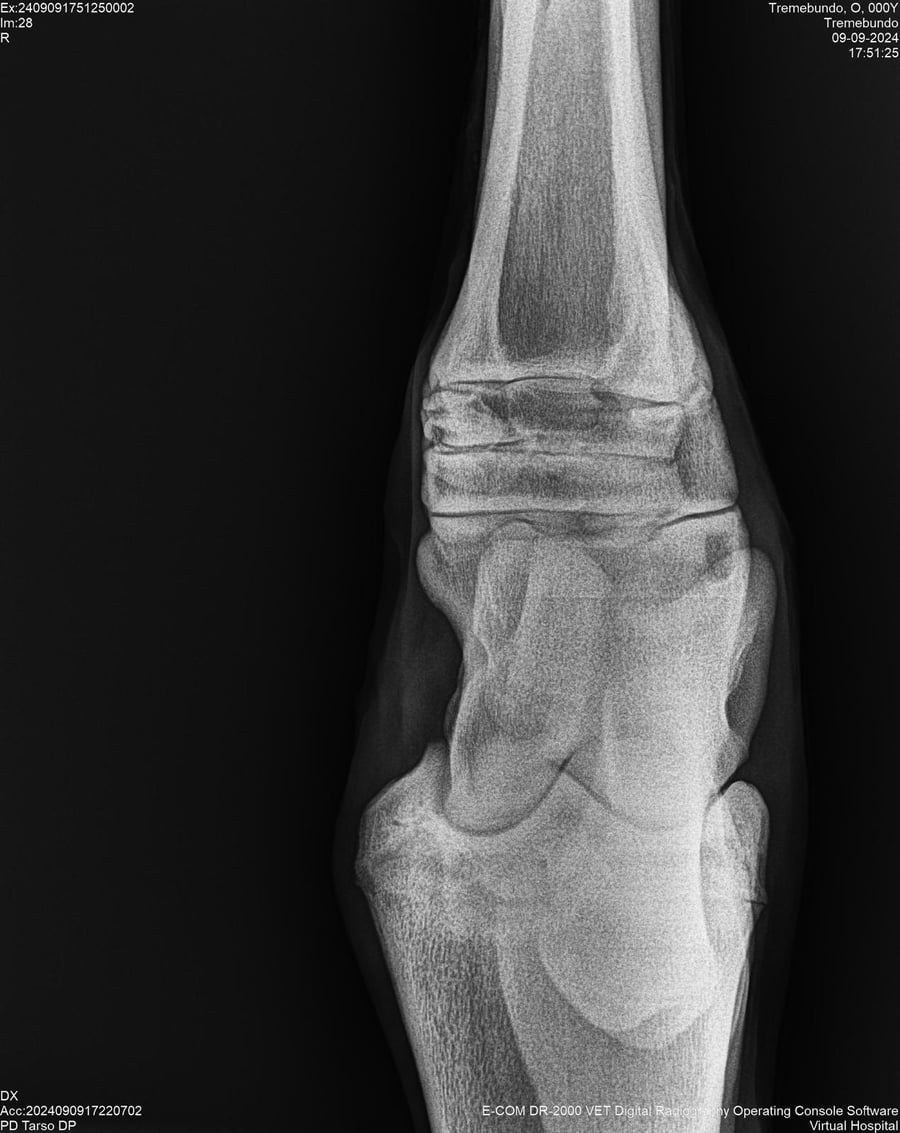

LOTE 37, TREMEBUNDO

Ficha del Lote

Identificador: #291140-

Generacion 2022